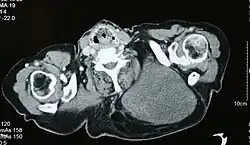

Tłuszczakomięsak, podobnie jak inne mięsaki jest wykrywany w badaniach obrazowych, z których największą rolę pełni rezonans magnetyczny (MRI). Ponadto, w przeciwieństwie do innych mięsaków tkanek miękkich, rozpoznanie tłuszczakomięsaka może być postawione poprzez badania obrazowe[29][30].

Badania obrazowe

Badaniem obrazowym mającym największe znaczenie dla postawienia rozpoznania tłuszczakomięsaka jest rezonans magnetyczny, a mniejszą przydatność wykazuje tomografia komputerowa (TK)[29][30]. Ta druga technika znajduje zastosowanie w diagnostyce przerzutów w płucach oraz zmian w przestrzeni pozaotrzewnowej, gdzie jej skuteczność jest porównywalna do rezonansu magnetycznego[31]. Do wstępnej diagnostyki może być stosowana ultrasonografia (USG)[31].

Tłuszczakomięsak dobrze zróżnicowany w rezonansie magnetycznym na ogół przypomina tkankę tłuszczową, podczas gdy guzy o niskim zróżnicowaniu są zmianami beztłuszczowymi[9]. Tłuszczakomięsak dobrze zróżnicowany przybiera formę słabo unaczynionego guza o intensywności sygnału odpowiadającemu tkance tłuszczowej, z grubymi przegrodami łącznotkankowymi zawierającymi guzkowate elementy nietłuszczowe[32][33][30]. W rezonansie magnetycznym w obrazach T1-zależnych wykazuje niski lub pośredni sygnał i wysoki sygnał w obrazach T2-zależnych. Zwykle guz jest dobrze odgraniczony[30].

Tłuszczakomięsak śluzowaty z powodu mniejszego odsetka tkanki tłuszczowej, charakteryzuje się dużą zawartością wody w tkankach guza, co jest wykrywalne w MRI, TK i USG. Wykrycie niewielkiej ilości tkanki tłuszczowej w przegrodach lub niewielkich zmianach ogniskowych umożliwia rozpoznanie 80–95% przypadków guza[32]. W tłuszczakomięsaku śluzowatym obraz zależy od ilości tkanki tłuszczowej, materiału śluzowatego, stopnia komórkowości, unaczynienia i martwicy. Tłuszczakomięsak śluzowaty w MRI w obrazach T1-zależnych zwykle wykazuje niski sygnał i obraz może zawierać w mniejszej proporcji wysoki sygnał[34]. W guzie występują koronkowe, linearne lub bezpostaciowe ogniska tkanki tłuszczowej[35]. W części z tych guzów w obrazie T1-zależnym nie uwidaczniają się strefy tłuszczowe i w tych guzach w obrazach T2-zależnych jest obserwowany homogenny lub heterogenny wysoki sygnał[34]. Przegrody mogą dawać słaby sygnał w obrazie T2-zależnym. Po podaniu kontrastu gadolinowego następuje wzmocnienie obrazu guza[35]. Guz jest dobrze odgraniczony[34].

Tłuszczakomięsak odróżnicowany typowo zawiera składniki o obrazie tłuszczakomięsaka dobrze zróżnicowanego oraz ogniskowe nietłuszczowe masy. Granice guza mogą być dobrze lub słabo odgraniczone. Guzy posiadają heterogenny lub mieszany niski, pośredni lub wysoki sygnał w obrazach T1 i T2-zależnych. W części nietłuszczowej mogą być widoczne krwotoki lub martwica. Po podaniu środka cieniującego guzy wykazują wybitne wzmocnienie kontrastowe o heterogennym wzorze[34]. Występowanie dominującej ogniskowej zmiany powyżej 1 cm w tłuszczakomięsaku dobrze zróżnicowanym sugeruje odróżnicowany tłuszczakomięsak[32].

Tłuszczakomięsak wielopostaciowy jest widoczny jako zmiany mięsakowate o wysokiem stopniu zróżnicowania, z niewielkimi ilościami tkanki tłuszczowej, które w 60–75% przypadków umożliwiają rozpoznanie[32]. Często są widoczne ogniska krwotoczne i martwica[9]. Cechują się mieszanym niskim, pośrednim lub wysokim sygnałem w obrazach T1 i T2-zależnych[34]. Po podaniu kontrastu guzy wykazują wybitne wzmocnienie kontrastowe o heterogennym wzorze[34].